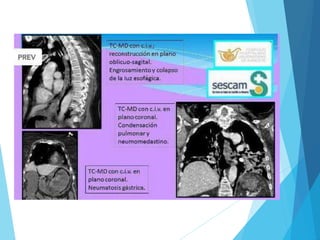

 Estudios radiológicos: - Fase aguda: Rx simple de tórax

 TAC con contraste oral (método mas sensible para

detectar una perforación incipiente).